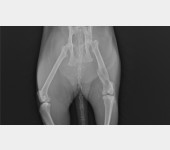

Trzy lata temu odłowiłam na osiedlu do sterylizacji dziką około 2letnią kotkę, która nazwaliśmy LUSI. Okazało się, że ma gorączkę, zapalenie płuc i inne przypadłości kota dziko - żyjącego. Z uwagi na konieczność leczenia, LUSIA zamieszkała z nami. Bardzo szybko zaadoptowała się do nowych warunków, więc została z nami. W tym roku zrealizowałam moje marzenie i przeprowadziłam się do mieszkania z ogródkiem. W trakcie prac wykończeniowych, przez nieuwagę pracownika wystraszona uciekła. Blisko 3 miesiące poszukiwałam ją bezskutecznie, aż do 18 marca Tego dnia szłam do domu i kotka słysząc mój głos, wyczołgała się z krzaków pod moje nogi ciągnąc za sobą tylną łapkę. Od razu udałam się do weterynarza i cios w serce... Okazało się, że LUSI została brutalnie, z wielką siłą potrącona przez samochód kilka tygodni wcześniej i pozostawiona w olbrzymim bólu i cierpieniu. Kotka po tym zdarzeniu zdziczała, ale nie dając za wygraną udałam się do znanego i polecanego specjalisty chirurga – ortopedy. Weterynarz zaleciła dalszą diagnostykę neurologiczną, leczenie farmakologiczne i dała nadzieję na wyzdrowienie kotki po zoperowaniu jej pękniętej miednicy i łapki. Niestety z uwagi na trudną sytuację finansową, nie jestem w stanie sama podołać tym kosztom. Bardzo proszę o wsparcie, abym mogła ulżyć kotce w cierpieniu.